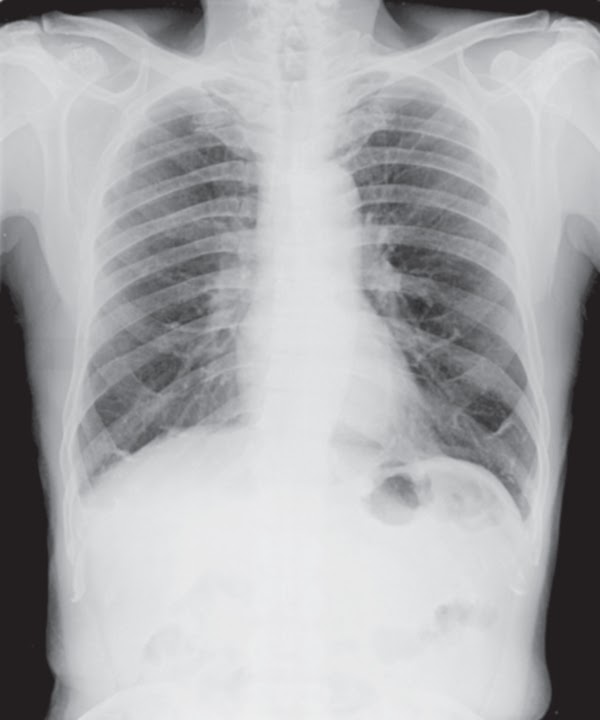

Chest XRay for the Diagnosis of Lung Cancer Can A Chest X Ray Detect Costochondritis Key sign is pain on. You or someone else has symptoms like: But a health care provider might order certain tests,. There is no laboratory or imaging test to confirm a diagnosis of costochondritis. The pain may be worse. md explores its origins, signs, diagnosis, and remedies. Costochondritis may cause sharp pain in the front or side of your chest.. Can A Chest X Ray Detect Costochondritis.

Chest Xray or XRay Image Of Human for detect heart disease and lung Can A Chest X Ray Detect Costochondritis md explores its origins, signs, diagnosis, and remedies. Costochondritis may cause sharp pain in the front or side of your chest. Check if you have costochondritis. The pain may be worse. But a health care provider might order certain tests,. You or someone else has symptoms like: Key sign is pain on. There is no laboratory or imaging test to. Can A Chest X Ray Detect Costochondritis.